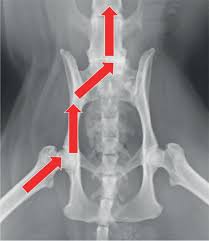

Two radiographic views of the cat's pelvis are used to confirm the diagnosis of pelvic fractures and may also show sacroiliac luxation (dislocation), coxofemoral luxation, or femoral fracture if they are present. The pelvis is the lower portion of the trunk, located between the abdomen and the lower limbs. The video covers the most clinic. Labelling by dr amaran parasuramar; ©ken l schreibman, phd/md 10/8/11 www.schreibman.info what to order when: The slice thickness is 2.5 mm. We created an anatomical atlas of abdominal and pelvic ct which is an interactive tool for studying the conventional anatomy of the normal structures based on a multidetector computed tomography. The following slides are from wikiradiography (wetpaint) here.